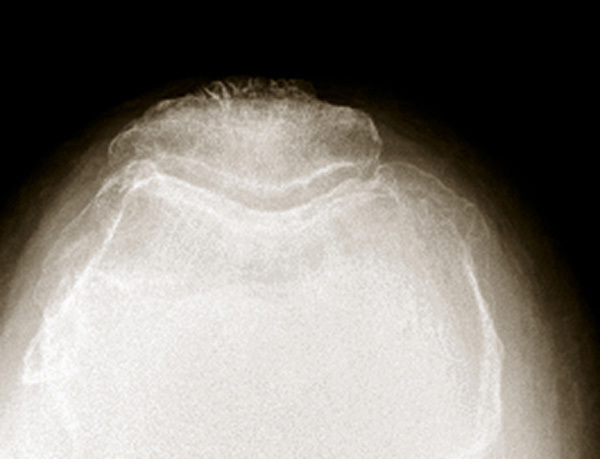

Radiologie d'une arthrose fémoro-patellaire. Sur les incidences axiales, on retrouve un amincissement ou une disparition de l’interligne externe, associés à une ostéophytose rotulienne trochléenne externe